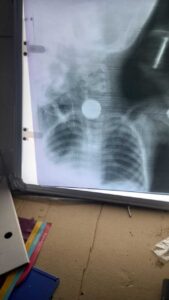

चार वर्षीय बालक ने निगला सिक्का, दुमका रेफर

प्रतिनिधि, गोपीकांदर गोपीकांदर प्रखंड के रांगा मिशन गांव में सोमवार सुबह चार वर्षीय राम मड़ैया के गले में सिक्का फंसने से परिजन घबरा गये, उसे सीएचसी गोपीकांदर लाये. बच्चे के पिता बाबूराम मड़ैया ने बताया कि सुबह करीब छह बजे बेटा खेलते समय मुंह पर रखा सिक्का निगल गया. खांसी आने पर जब मुंह देखा गया तो सिक्का गले में फंसा मिला. काफी प्रयास के बावजूद सिक्का नहीं निकला तो उसे अस्पताल ले जाया गया. सीएचसी गोपीकांदर के डॉक्टर सुमित आनंद ने जांच और एक्स-रे के बाद सिक्का निकालने के लिए बेहतर इलाज के लिए बच्चे को पीजेएमसीएच रेफर कर दिया. हालांकि रेफर के दौरान बड़ी लापरवाही सामने आयी. अस्पताल में मौजूद ममता वाहन का ड्राइवर नहीं मिला. एंबुलेंस चालक ने बताया कि गोपीकांदर के लिए एंबुलेंस उपलब्ध नहीं है. पेट्रोल की कमी के कारण भी वाहन नहीं मिला. नतीजा यह हुआ कि गंभीर स्थिति में बच्चे को यात्री बस से दुमका भेजना पड़ा. राइस अगेंस्ट हंगर इंडिया की कार्यक्रम पर्यवेक्षिका सुभाष लकड़ा की आर्थिक मदद से परिजनों ने बच्चे को दुमका पहुंचाया गया. ग्रामीणों ने कहा कि स्वास्थ्य विभाग द्वारा स्वस्थ नारी सशक्त, परिवार अभियान जैसे बड़े कार्यक्रम चलाए जा रहे हैं, लेकिन आपात स्थिति में एंबुलेंस और ममता वाहन उपलब्ध नहीं होना विभाग की बड़ी नाकामी है.